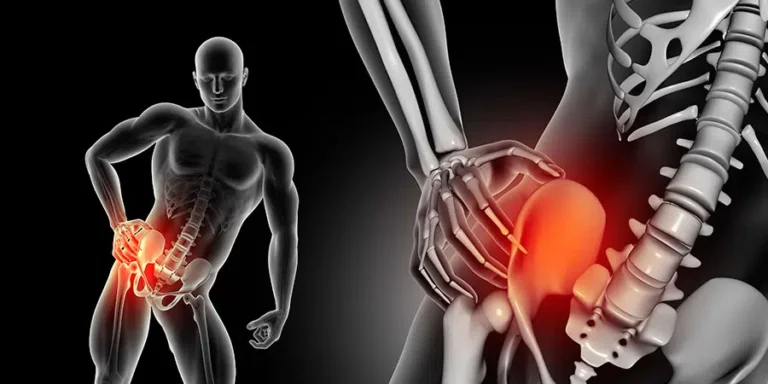

Conoce más sobre la Trocanteritis

Dolor en la cadera que no desaparece: ¿es trocanteritis u otra cosa? Tienes un dolor persistente en...

¿Es normal tener trocanteritis durante meses sin mejoría? Llevas meses con un dolor en la parte...

Trocanteritis crónica: lo que nadie te explicó sobre su origen y solución Vives con un dolor...